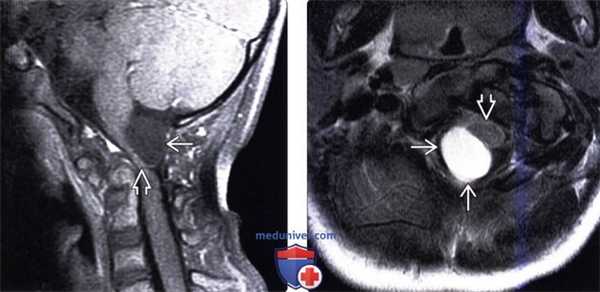

(а) МРТ, Т1-ВИ, сагиттальный срез: визуализируется типичная нейроэнтерическая киста в виде хорошо очерченного гиперинтенсивного объемного образования овоидной формы, локализующегося парамедианно кпереди от понтомедуллярного перехода.

(б) МРТ, Т1-ВИ, режим подавления сигнала от жира, аксиальный срез: у этого же пациента определяется, что объемное образование распространяется в нижнелатеральном направлении кпереди от нижних отделов продолговатого мозга. Центральные отделы объемного образования слегка смещены от срединной линии, что типично для нейроэнтерической кисты задней черепной ямки.

3. МРТ признаки нейроэнтерической кисты:

• Т1-ВИ:

о Практически всегда изо-/гиперинтенсивный по отношению к СМЖ сигнал

• Т2-ВИ:

о 90% НЭК имеют гиперинтенсивный, 10%-гипоинтенсивный по отношению к СМЖ сигнал

• FLAIR:

о Гиперинтенсивный по отношению к СМЖ сигнал

• ДВИ:

о Обычно ограничение диффузии отсутствует, но возможно его выявление в небольшой степени

• Постконтрастные Т1-ВИ:

о Обычно контрастирование отсутствует; иногда слабоинтенсивное ободковое контрастное усиление